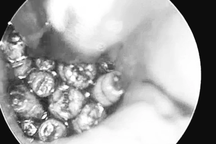

Tại Bệnh viện Tai Mũi Họng Trung ương, sau khi tiến hành nội soi, các bác sĩ phát hiện nhiều dị vật màu trắng di động là những con giòi lúc nhúc lấp đầy hòm nhĩ người bệnh. Các bác sĩ đã gắp ra hơn chục con giòi tại chỗ.

Những con giòi gắp từ bên trong tai của bệnh nhân (Ảnh: Bệnh viện cung cấp).

Ngày hôm sau, các bác sĩ đã thực hiện phẫu thuật nội soi, gắp hàng chục con giòi sống và lấy sạch tổ chức viêm trong tai giữa của bệnh nhân. Hiện tại, tình trạng tai của người bệnh đã ổn định, người bệnh phục hồi nhanh và đã xuất viện.